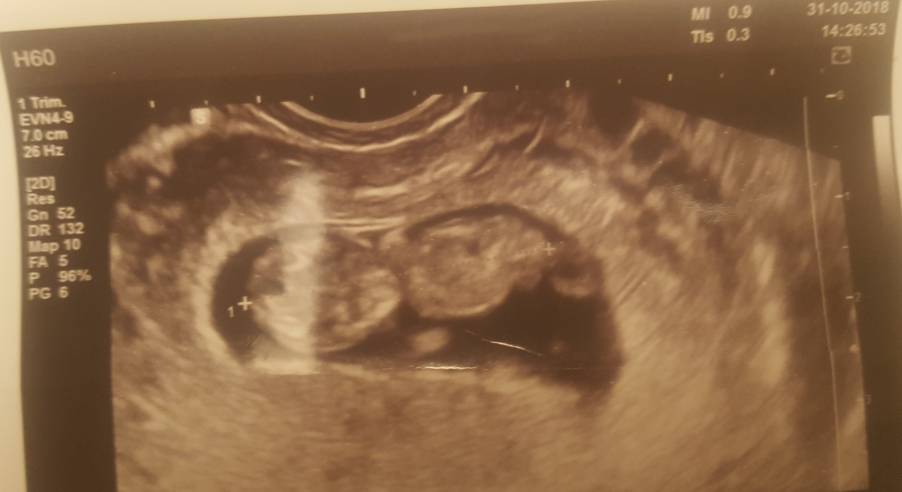

No i jest moja fasola[emoji7]

Na 80% będzie chłopczyk.

20181031_182725.jpg